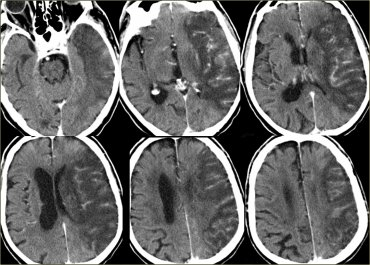

Stroke Syndrome:

ACA stem occlusion in the A2 segment (distal to the ACOM). In this case, the right A2 is involved.

If the left A2 segment is involved, you might see an alien hand too